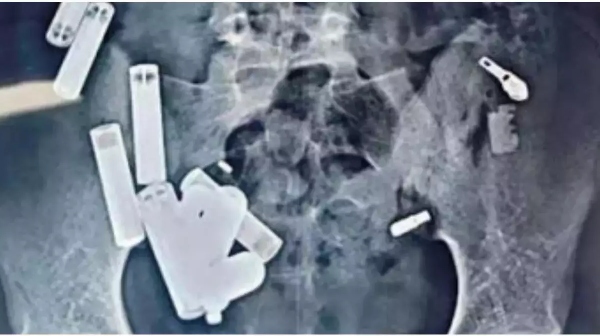

உத்திரப்பிரேதேச மாநிலம், ஹத்ராஸைச் சேர்ந்தவர் ஆதித்யா சர்மா. 14 வயது சிறுவனான ஆதித்யா சர்மா அப்பகுதியில் உள்ள பள்ளியில் 9 ஆம் வகுப்பு படித்து வந்துள்ளார். இந்நிலையில், வயிற்றில் ஏற்பட்ட வலி காரணமாக டெல்லி சப்தார்ஜங் மருத்துவமனைில் சிறுவன் அனுமதிக்கப்பட்டுள்ளார். அப்போது, சிறுவனின் வயிற்றைப் பரிசோதித்தபோது பிளேடு, ஸ்க்ரூ, பேட்டரி என 65 மெட்டல் பொருட்கள் இருப்பதும், நோய்த்தொற்று ஏற்பட்டிருப்பதும் தெரியவந்துள்ளது.

இதையடுத்து, மருத்துவர்கள் 5 மணி நேரத்துக்கும் மேலாக சிறுவனுக்கு அறுவை சிகிச்சை செய்து 65 பொருள்களையும் சிறுவனின் வயிற்றில் இருந்து அகற்றிய நிலையில், சிறுவன் உயிரிழந்துள்ள சம்பவம் பரபரப்பை ஏற்படுத்தியுள்ளது. இதுகுறித்து மருத்துவர்கள் கூறுகையில், சிறுவன் கடந்த காலங்களில் இந்தப் பொருள்களை எல்லாம் விழுங்கியிருக்கலாம். அதனால், நோய்த் தொற்று ஏற்பட்டு உயிரிழந்துள்ளார் என்று தெரிவித்துள்ளனர்.

அதனை மருத்துவர்கள் உடனடியாக சரிசெய்தனர். அதன் பிறகு அக்டோபர் 26 ஆம் தேதி ஆதித்யாவுக்கு வயிற்றுவலி ஏற்பட்டது. அப்போது அல்ட்ரா சவுண்ட் பரிசோதனை செய்து பார்த்தபோது 19 பொருட்கள் வயிற்றுக்குள் சிக்கியிருப்பது தெரியவந்தது. இதையடுத்து, உடனடியாக நொய்டாவில் உள்ள தனியார் மருத்துவமனைக்கு பரிந்துரை செய்தனர்.

உடனடியாக நொய்டா மருத்துவமனைக்கு சென்று பார்த்தபோது 42 பொருட்கள் சிறுவனின் வயிற்றுக்குள் இருப்பதாகவும் உடனடியாக சிகிச்சை அளிக்க வேண்டும் என்று மருத்துவர்கள் கூறினர். இதையடுத்து, டெல்லி சப்தார்ஜங்கில் உள்ள மருத்துவமனைக்கு அழைத்துச் சென்று பார்த்தபோது 65 பொருள்கள் சிறுவனின் வயிற்றில் இருப்பது தெரியவந்தது.